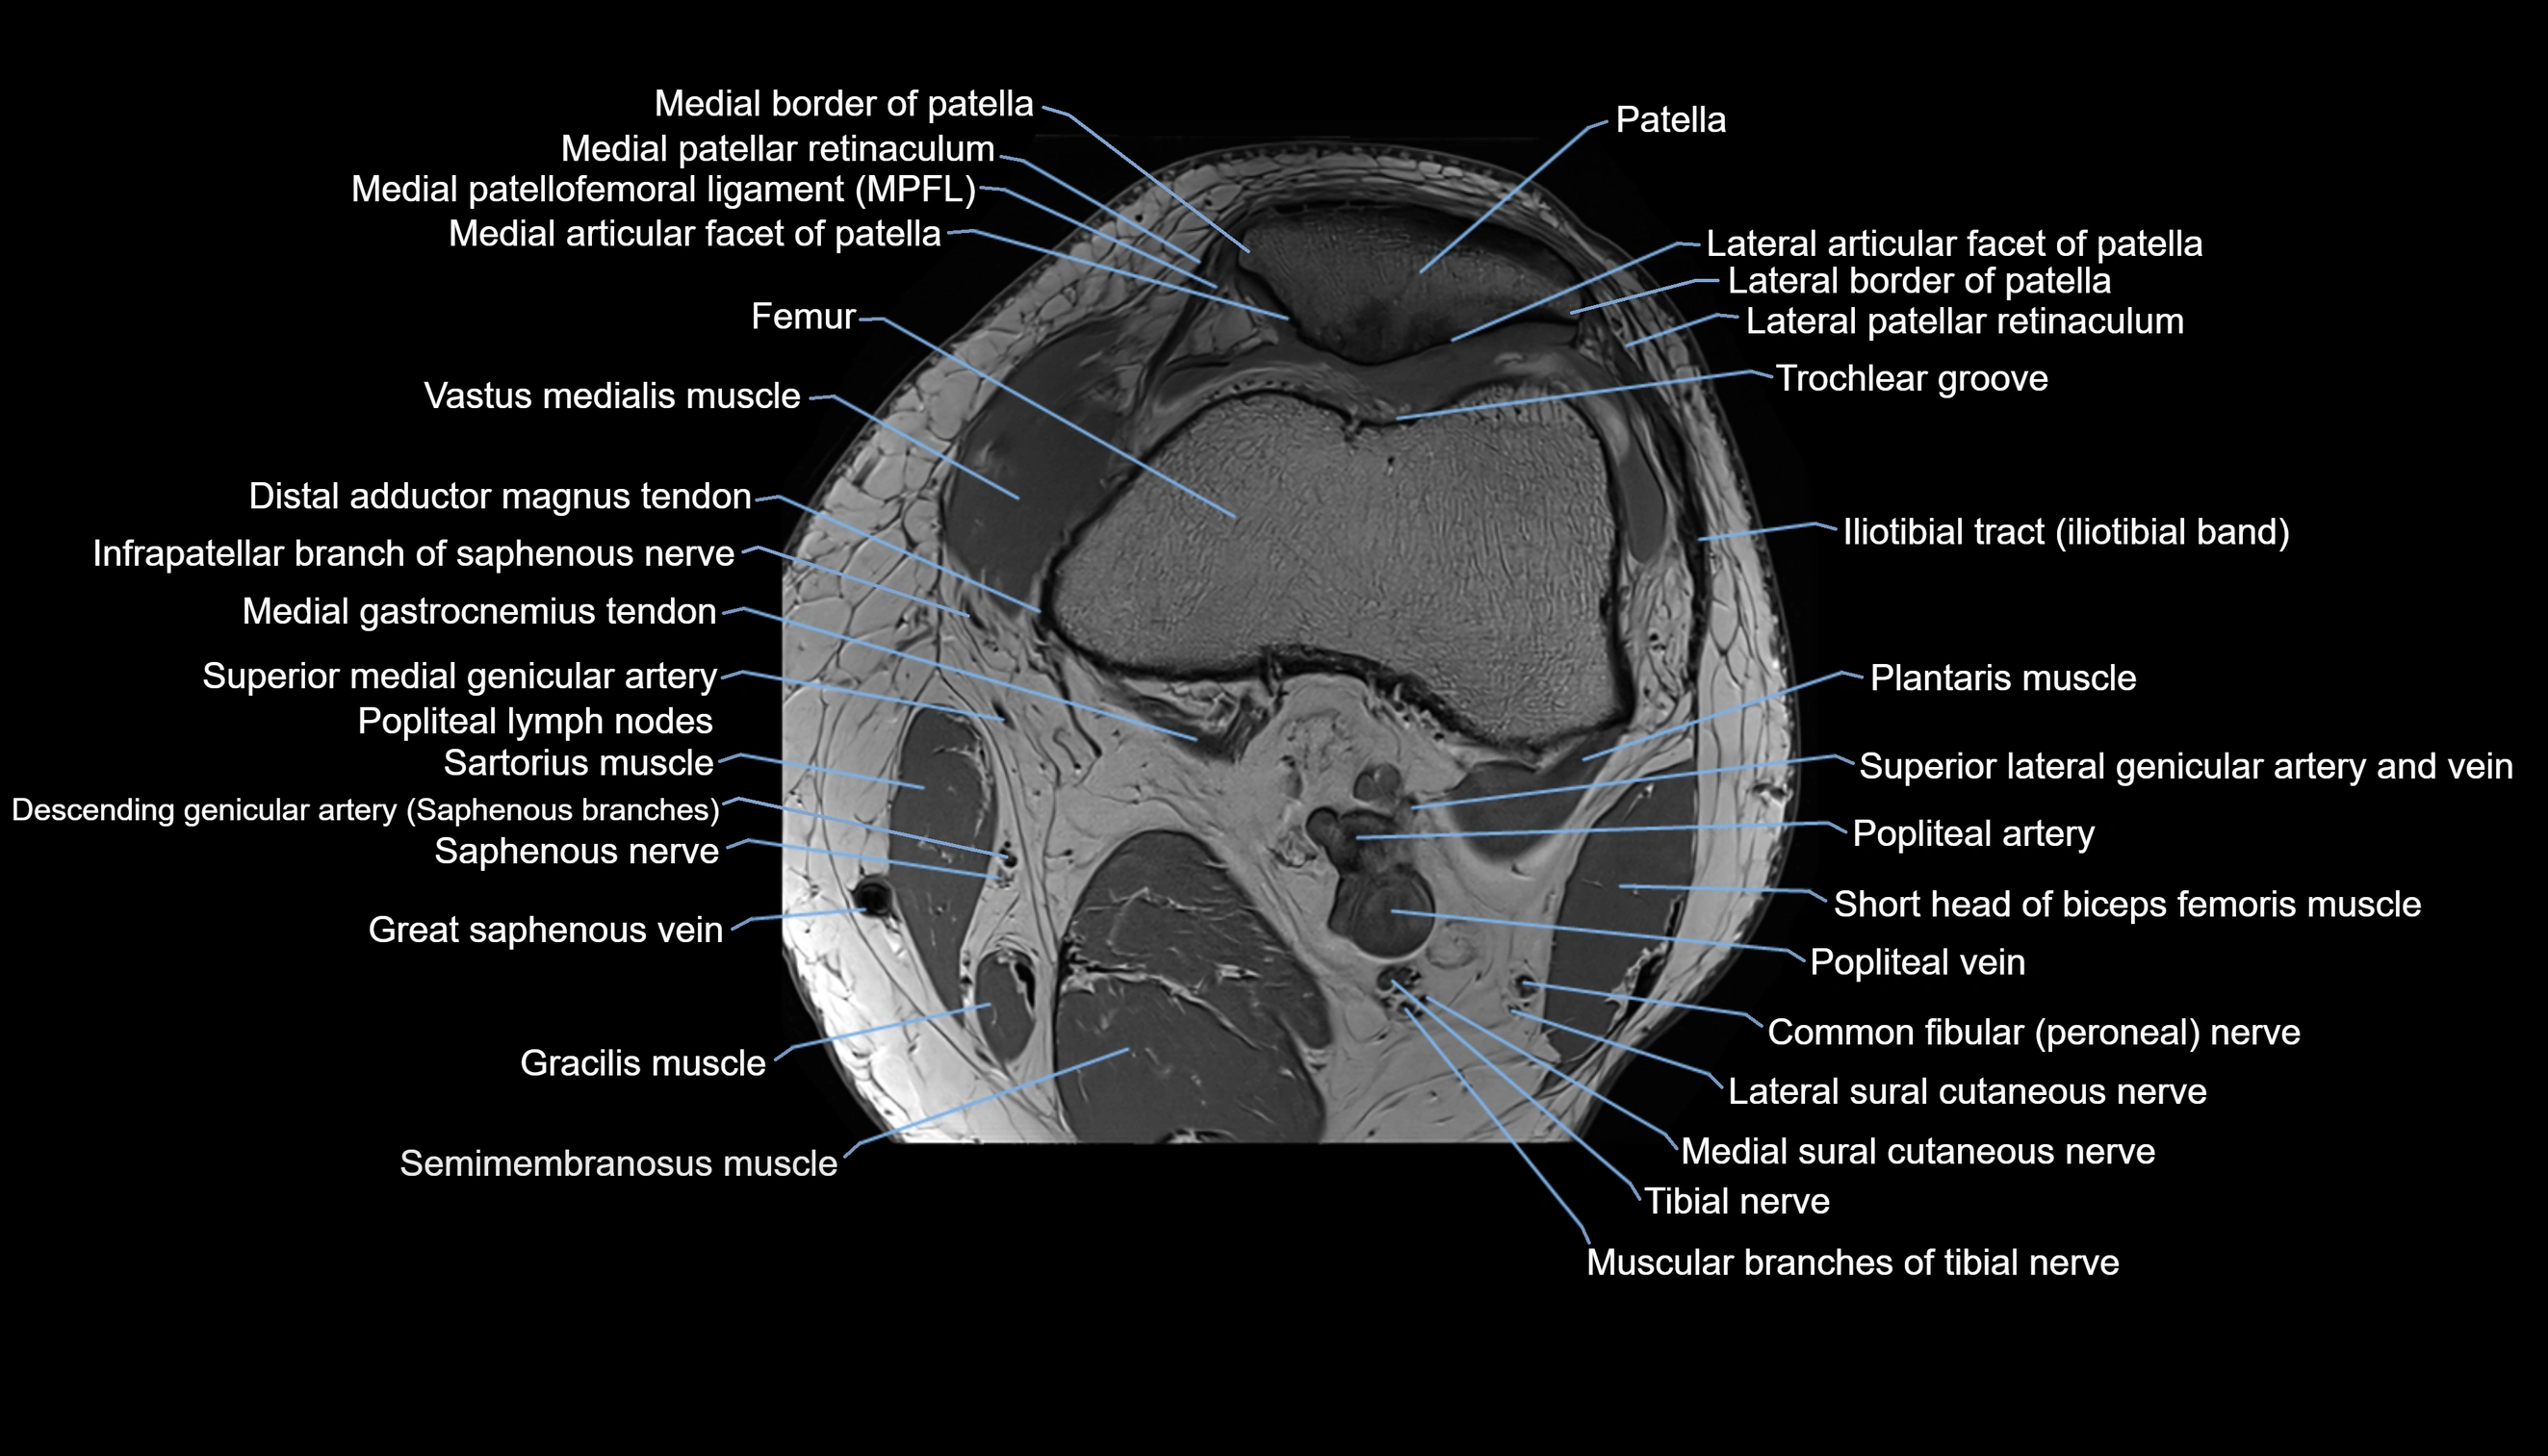

- Lateral articular facet of patella

- Lateral border of patella

- Lateral patellar retinaculum

- Lateral patellofemoral ligament

- Medial articular facet of patella

- Medial border of patella

- Medial patellar retinaculum

- Medial patellofemoral ligament

- Patella

- Trochlear groove

- Vastus medialis muscle

- Popliteal lymph nodes

- Popliteal vein

- Popliteal artery

- Lateral sural cutaneous nerve

- Medial sural cutaneous nerve

- Muscular branches of tibial nerve

- Tibial nerve

- Plantaris muscle

- Sartorius muscle

- Semimembranosus muscle

- Medial gastrocnemius tendon

- Distal adductor magnus tendon

- Infrapatellar branch of saphenous nerve